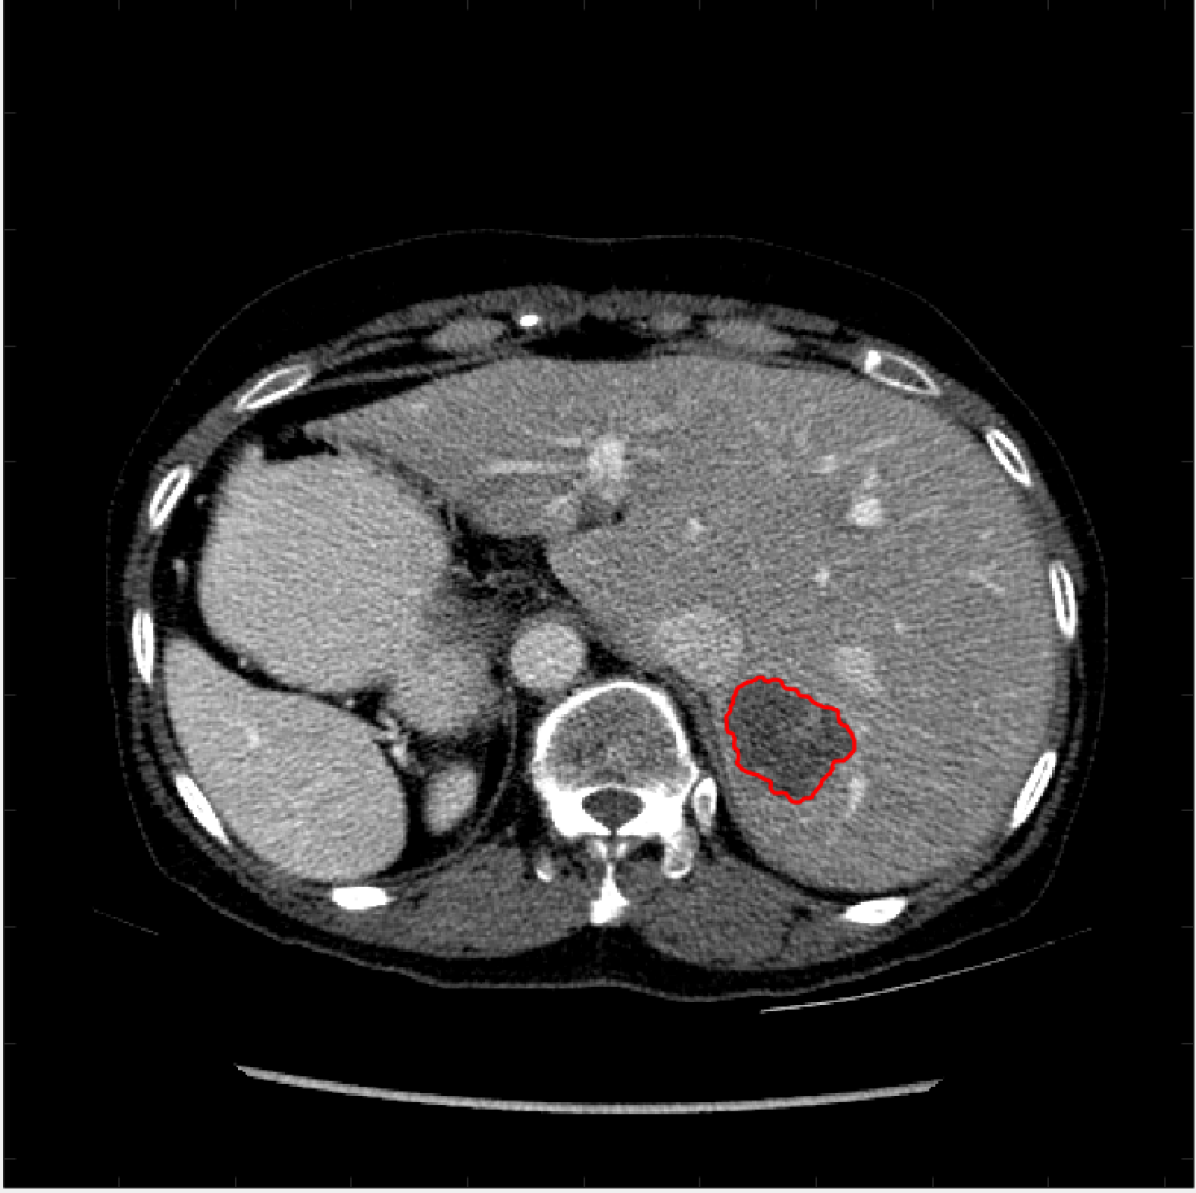

Figure 5: A sample result on the Liver data. We display the input image with the user input \mathcal{M}, the ground truth (GT) and results from the four methods. Moreover, we show comparisons with the model (4) solved in a variational framework with both Total Variation (TV) and Euler Elastica as explicit regularisation, as well as a comparison with the model solved in a Deep Image Prior framework.

Figure 6: A sample result on the Liver data. We display the input image with the user input \mathcal{M}, the ground truth (GT) and results from the four methods. Moreover, we show comparisons with the model (4) solved in a variational framework with both Total Variation (TV) and Euler Elastica as explicit regularisation, as well as a comparison with the model solved in a Deep Image Prior framework.